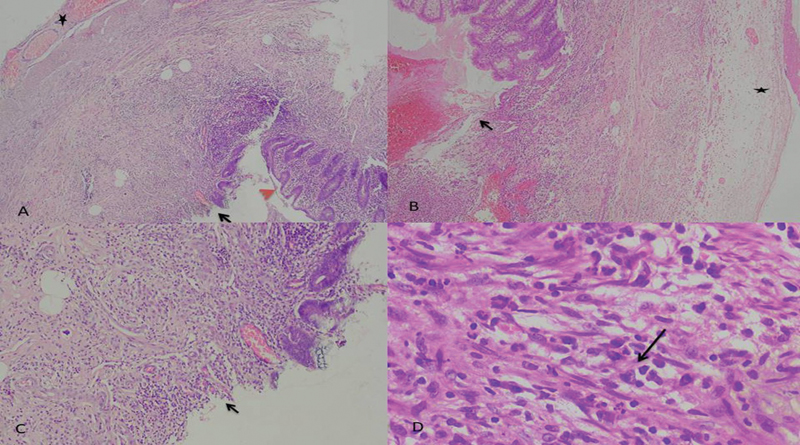

Fig. 1 (A, B)Axial and coronal postcontrast images showing a dilated appendix (arrow) in the right iliac fossa with significant peri-appendiceal fat stranding in keeping with acute appendicitis.